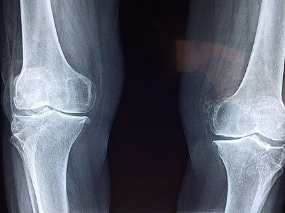

만약 가정에서의 치료로도 무릎통증이 완화되지 않는다면 전문가의 도움을 받아야 합니다. 전문가는 무릎통증의 원인과 심각도에 따라 적절한 치료법을 제시해줄 것입니다. 치료법으로는 약물치료, 물리치료, 수술치료 등이 있습니다. 전문가의 도움을 받아 적절한 치료를 받으면 무릎통증을 완화시킬 수 있습니다.